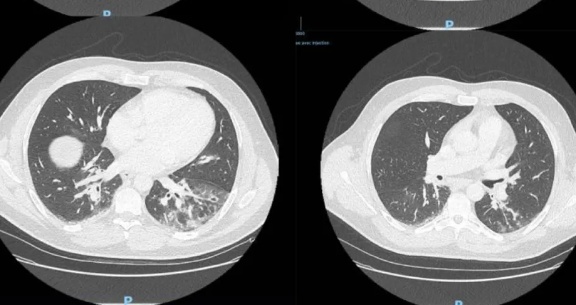

最新!法国这个病人发病前无临近旅行史与中国无关联